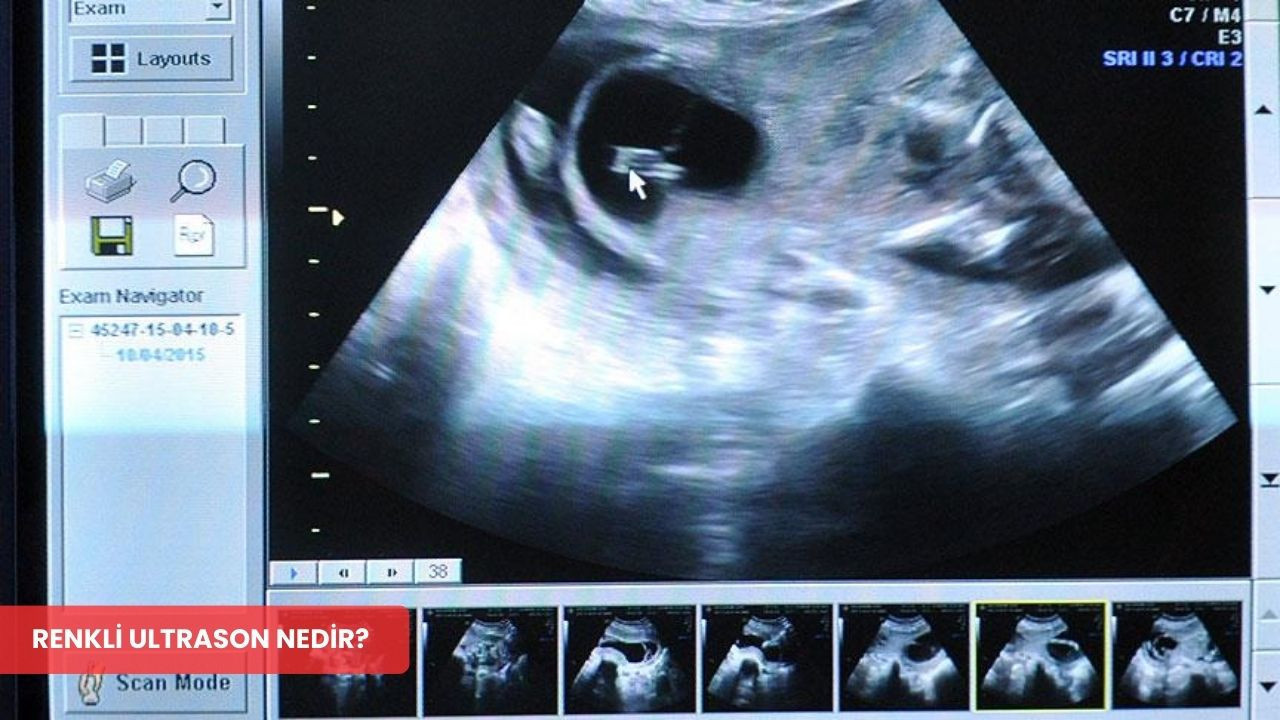

RENKLİ ULTRASON NEDİR?

Renkli ultrason, modern tıpta oldukça yaygın bir şekilde kullanılan ve vücuttaki kan akışını görüntülemeyi mümkün kılan bir tanı yöntemidir. Bu teknik, ultrasondan yansıyan ses dalgalarının analiz edilmesiyle çalışır. Böylece, damar içindeki kanın hareketi farklı renk tonlarıyla ekran üzerinde gösterilir. Bu renkli gösterim sayesinde doktorlar, damar yapıları hakkında daha detaylı bilgi edinebilir ve özellikle kalp-damar hastalıklarının teşhisinde kullanılır.

Renkli ultrason teknolojisi, geleneksel ultrason tekniklerine kıyasla daha detaylı bilgi sağlayarak, organ ve dokulardaki kan akışını etkili bir biçimde görüntüler. Kullanılan bu gelişmiş teknoloji, tıbbi teşhislerdeki doğruluk oranını arttırmakta ve sağlık profesyonellerine daha ayrıntılı veriler sunmaktadır. Özellikle kalp ve damar hastalıklarının teşhisinde büyük önem taşıyan renkli ultrasonun, tanı süreçlerini kolaylaştırdığı bilinmektedir. Bu teknoloji sayesinde, mevcut sağlık sorunlarının daha hızlı ve doğru bir şekilde tespit edilmesi mümkün olmaktadır.

- Görselleştirilecek alanın üzerinde prob dikkatlice gezdirilir.

- Renkli ultrason görüntüsü, cihaz ekranında canlı olarak izlenir ve kayıt altına alınır.